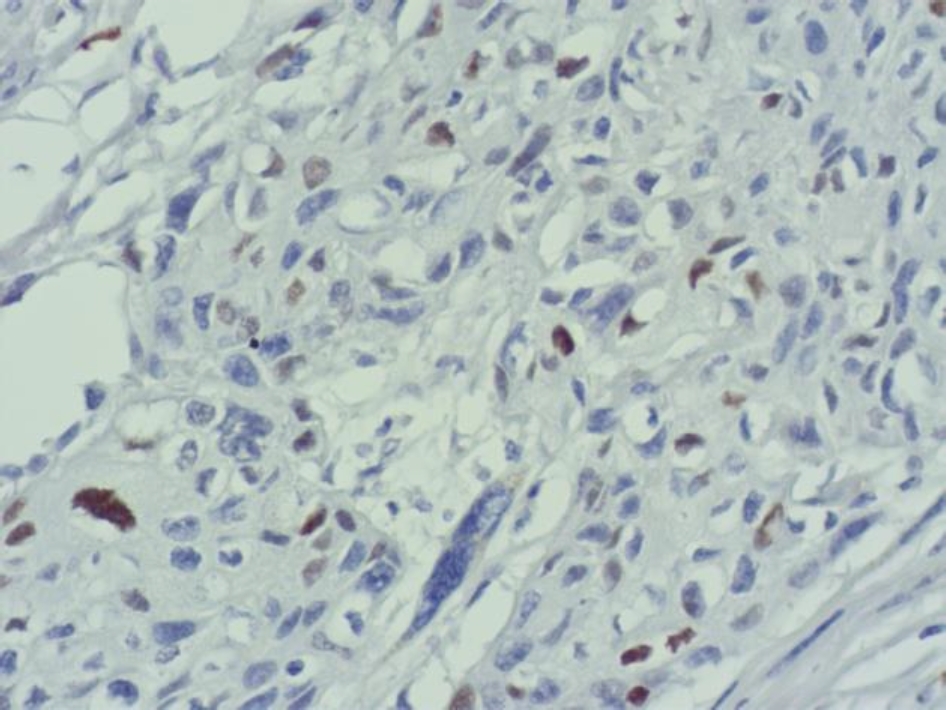

Экспрессия Cyclin D1 всех анализируемых наблюдений была очаговой, слабой и умеренной (рис. 4).

Рис. 4. Очаговая слабая и умеренная экспрессия Cyclin D1 в клетках плоскоклеточного рака языка. ИГХ окрашивание, ×400

Количество опухолевых клеток с амплификацией гена CCND1 в наших наблюдениях составило от 1 до 87, при этом гиперэкспрессии белка Cyclin D1 не определялось, экспрессия была очаговой, слабой и умеренной. По данным исследователей амплификация протоонкогена CCND1 при раке ротовой полости зависит от локализации, в частности, при раке языка составляет 88 [11] и 56,5 % [12], при плоскоклеточном раке щеки – 56 % [11], однако количество клеток с амплификацией не изучалось. В случаях разных категорий и степеней опухолевой дифференцировки определялась очаговая, слабая и умеренная экспрессия белка Cyclin D1, независимо от количества клеток с амплификацией протоонкогена CCND1. В работе исследователей также отсутствовала корреляционная связь между амплификацией CCND1 и экспрессией белка Cyclin D1 в случае плоскоклеточном раке полости рта [13].